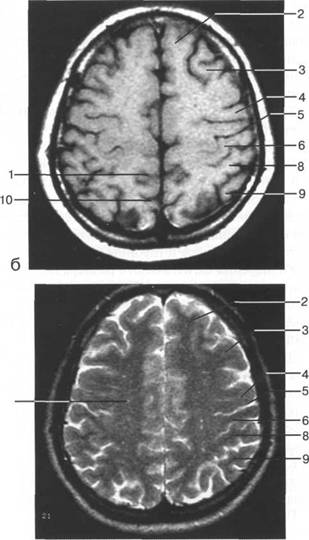

ные извилины (рис. 1.10). Структуры средней череп 13513u2010n 85;ой ямки ограничены спереди малым крылом основной кости, снизу - большим крылом, сзади - передней поверхностью пирами «edge» «bone»

Содержимое средней череп 13513u2010n 85;ой ямки представлено базальными отделами височной доли.

цистерна четверохолмия; 14 -прямой синус; 15 -лобный рог; 16 - головка хвостатого ядра; 17 -перед

III ди зрительного бугра идет ретроталамическая цистерна, ориентированная во фронтальной

теменно-затылочная борозда; 11 - семиовальные